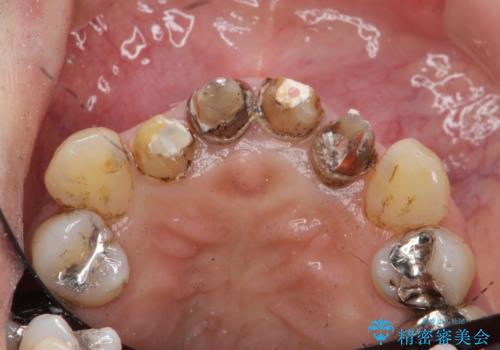

- クラウン周りの黒ずみが気になり、審美性の改善を求めて来院されました。

以前に治療した前歯クラウンは月日が経過することで劣化・歯肉の位置変化を引き起こし審美障害を引き起こしています。

劣化したクラウンを除去し、再発した虫歯を徹底的に除去したのち根管治療・ファイバーコア築盛を行いジルコニアクラウン製作へと移ります。